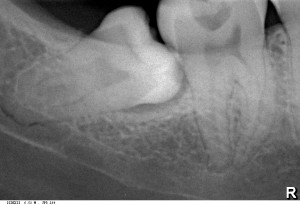

Удаление зуба мудрости на левом снимке обошлось пациенту в 4827 рублей. Удаление зуба мудрости пациенту на правом снимке обошлось пациенту в 4516 рублей, несмотря на то, что технически сделать это сложнее, а сама операция требует больше расходников и трудозатрат.

По действующему прейскуранту клиники («Канадская Стоматология») удаление данных зубов обходится немногим более 6000 рублей. Можно убедиться на стойке у администратора.

А все потому, что зуб на правом снимке принадлежит человеку с ограниченными финансовыми возможностями, который, к тому же, попросил сделать удаление зуба подешевле. Ну и, потому что пациент понравился — очень приятный человек. Я бы сделал данное удаление вообще бесплатным — но у меня есть некоторые обязательства перед моим работодателем и моей семьей. К тому же, я должен нормально жить и периодически учиться — а это тоже стоит каких-то денег.